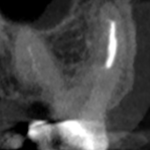

Pre-op

Post-op